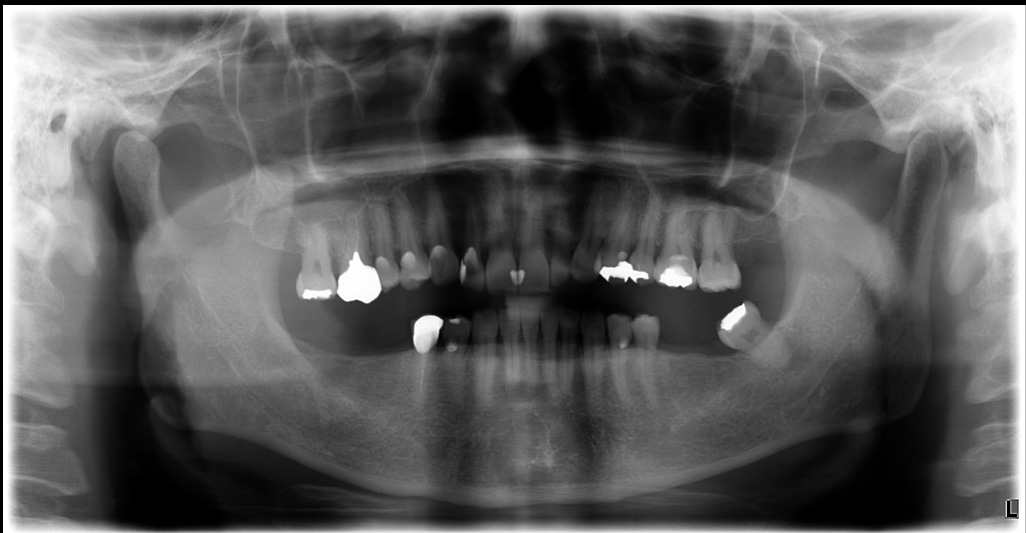

治療前